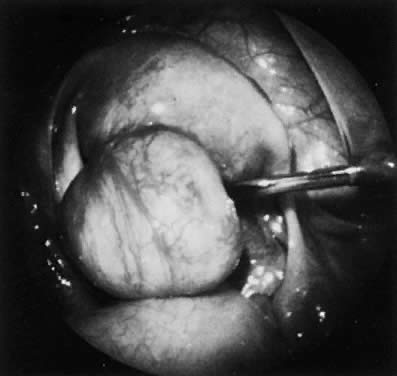

Uterine leiomyomas are usually spherical masses of tissue that can vary from a few millimeters to many centimeters in diameter. They may grow large enough to obstruct the ureters, compress the great vessels, or compromise of pulmonary ventilation. On dissection, myomas appear to have a capsule. The cells on the edge of the tumor seem to become flattened in the concentric pattern, leading to the clinical impression of a capsule, although there is no distinct fibrous tissue capsule microscopically (Fig. 1). Nevertheless, the pseudocapsule layer is the preferential plane of dissection to peel out the main mass of the myoma from the surrounding, more normal myometrium. The blood supply enters at the periphery of the tumor and the core is relatively avascular, which is the probable reason for the various forms of degeneration and necrosis that are seen in the center of some myomas.

Fig. 1. A. Intramural leiomyoma with whorled arrangement of smooth muscle cells on a matrix of connective tissue cells (×200). B. Notice the absence of distinct connective tissue capsule (×175). ( A and B, 66% of original magnification.)